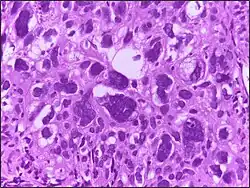

Large cell

Large cell is a term used in oncology. It does not refer to a particular type of cell; rather it refers to cells that are larger than would be normally expected for that type. It is frequently used when describing lymphoma and lung cancer.

The phrase giant cell is also frequently used, especially with carcinoma.